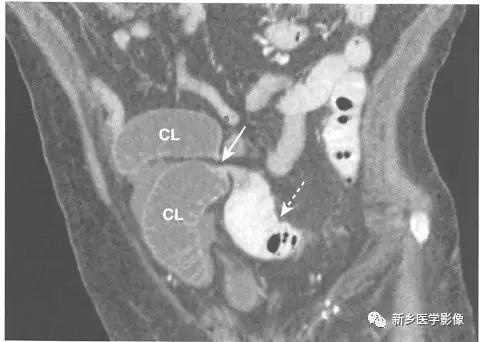

梗阻近端可见小肠肠襻扩张且腔内充满液体(直径>2.5cm )。

识别移行点,即肠道管径由扩张到正常的地方,提示梗阻部位。 如果在移行点未看到明确肿块或其他梗阻原因,则几乎可以肯定为粘连所致。

梗阻远端的小肠或结肠肠腔塌陷。

小肠粪便征。 小肠梗阻移行点近端的肠道内聚集肠道碎片和液体,形成类似粪便的外观,是小肠梗阻的征象。

闭襻性肠梗阻指同一肠襻的两个点在同一位置发生梗阻,闭襻通常形成U形或C形的扩张肠襻。 大多数的闭襻性肠梗阻由粘连所致。 小肠的闭襻性肠梗阻发生肠绞窄的风险更高。 大肠的闭襻性肠梗阻被称为肠扭转。